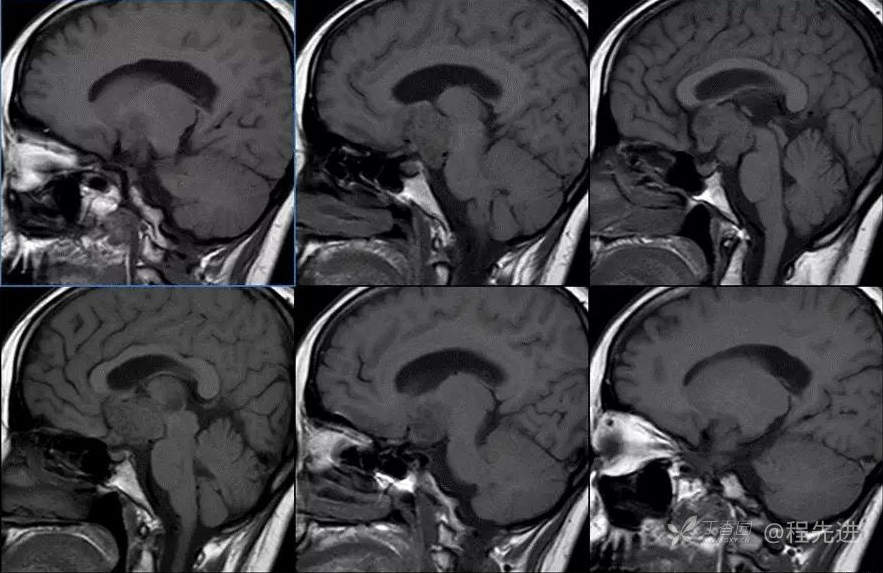

图像依次为T1横断位、T2横断位、T2FLAIR横断位、T2冠状、T1矢状、T1增强横断、矢状、冠状位